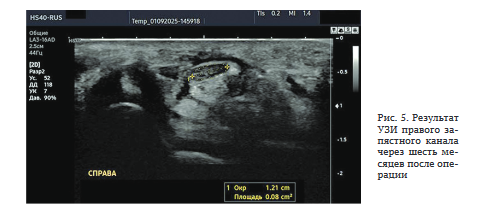

Результат УЗИ: ППС срединного нерва в запястном канале — 8 мм2 (рис. 5).

Таким образом, данное клиническое наблюдение иллюстрирует положительный результат своевременного, адекватного оперативного вмешательства по поводу идиопатического СЗК, в результате которого мышцы тенара, занимавшие более половины передней поверхности ПСЗ, фактически были сохранены, — первоначально аккуратно отслоены от связки, а затем заново прикреплены к ней.